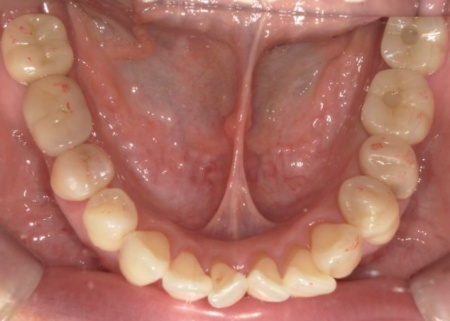

また、右下奥歯には、両隣の歯を土台にして橋を渡すように欠損部を補う被せ物「ブリッジ」が装着されていました。

右下奥歯は2本欠損しており、親知らず(第3大臼歯)と手前の奥歯(第2小臼歯)の2本でブリッジを支えていますが、これは親知らずに過度な負荷がかかる構造です。

親知らずはすでに大きく傾いており、こちらも温存が難しいため、ブリッジを除去してから親知らずを抜く必要があります。

以上のことから、ブリッジの除去と併せて、温存が難しい左上奥歯2本と右下の親知らず1本を抜き、欠損部位を補う治療を検討する必要があると診断しました。